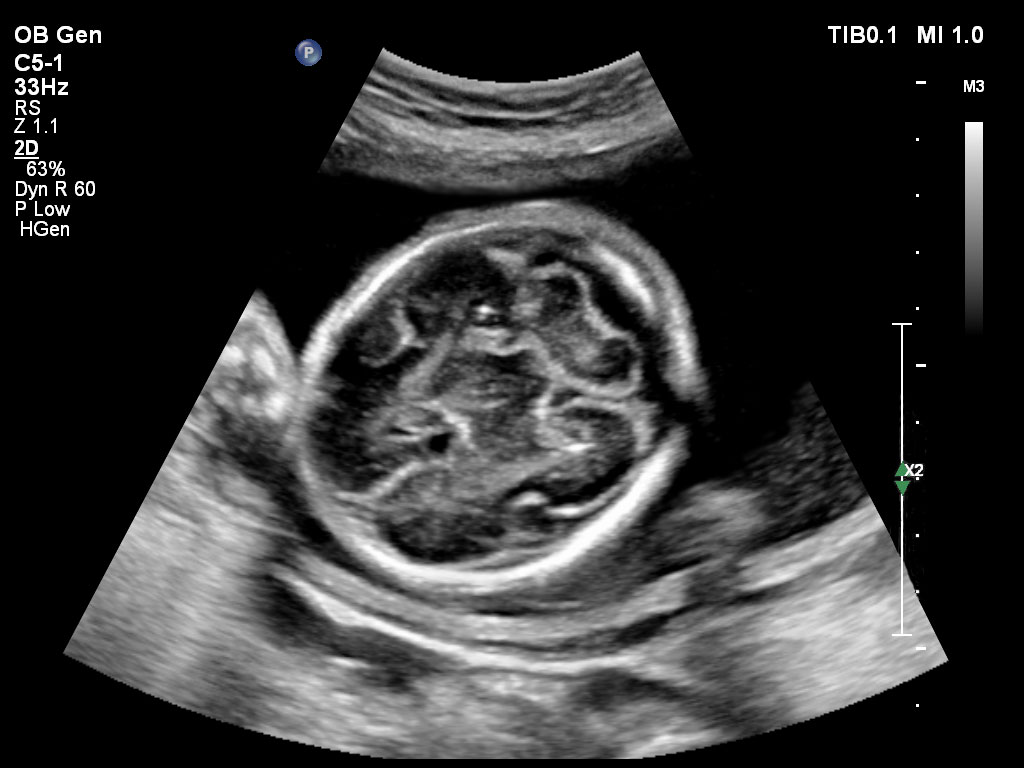

Bildgebung im 1. Trimenon

Überzeugende Bildgebung in allen Schwangerschafts­dritteln

Die EPIQ-Produktreihe mit ausgereiften Schallköpfen erfüllt die Anforderungen auch Ihrer anspruchsvollsten gynäkologischen Untersuchungen und während der gesamten Schwangerschaft.

• C5-1 PureWave-Breitband-Convex-Schallkopf für hohe Eindringtiefen in der Gynäkologie und der Geburtshilfe, für Patientinnen mit Schwangerschaftsdiabetes oder vorzeitigem Blasensprung